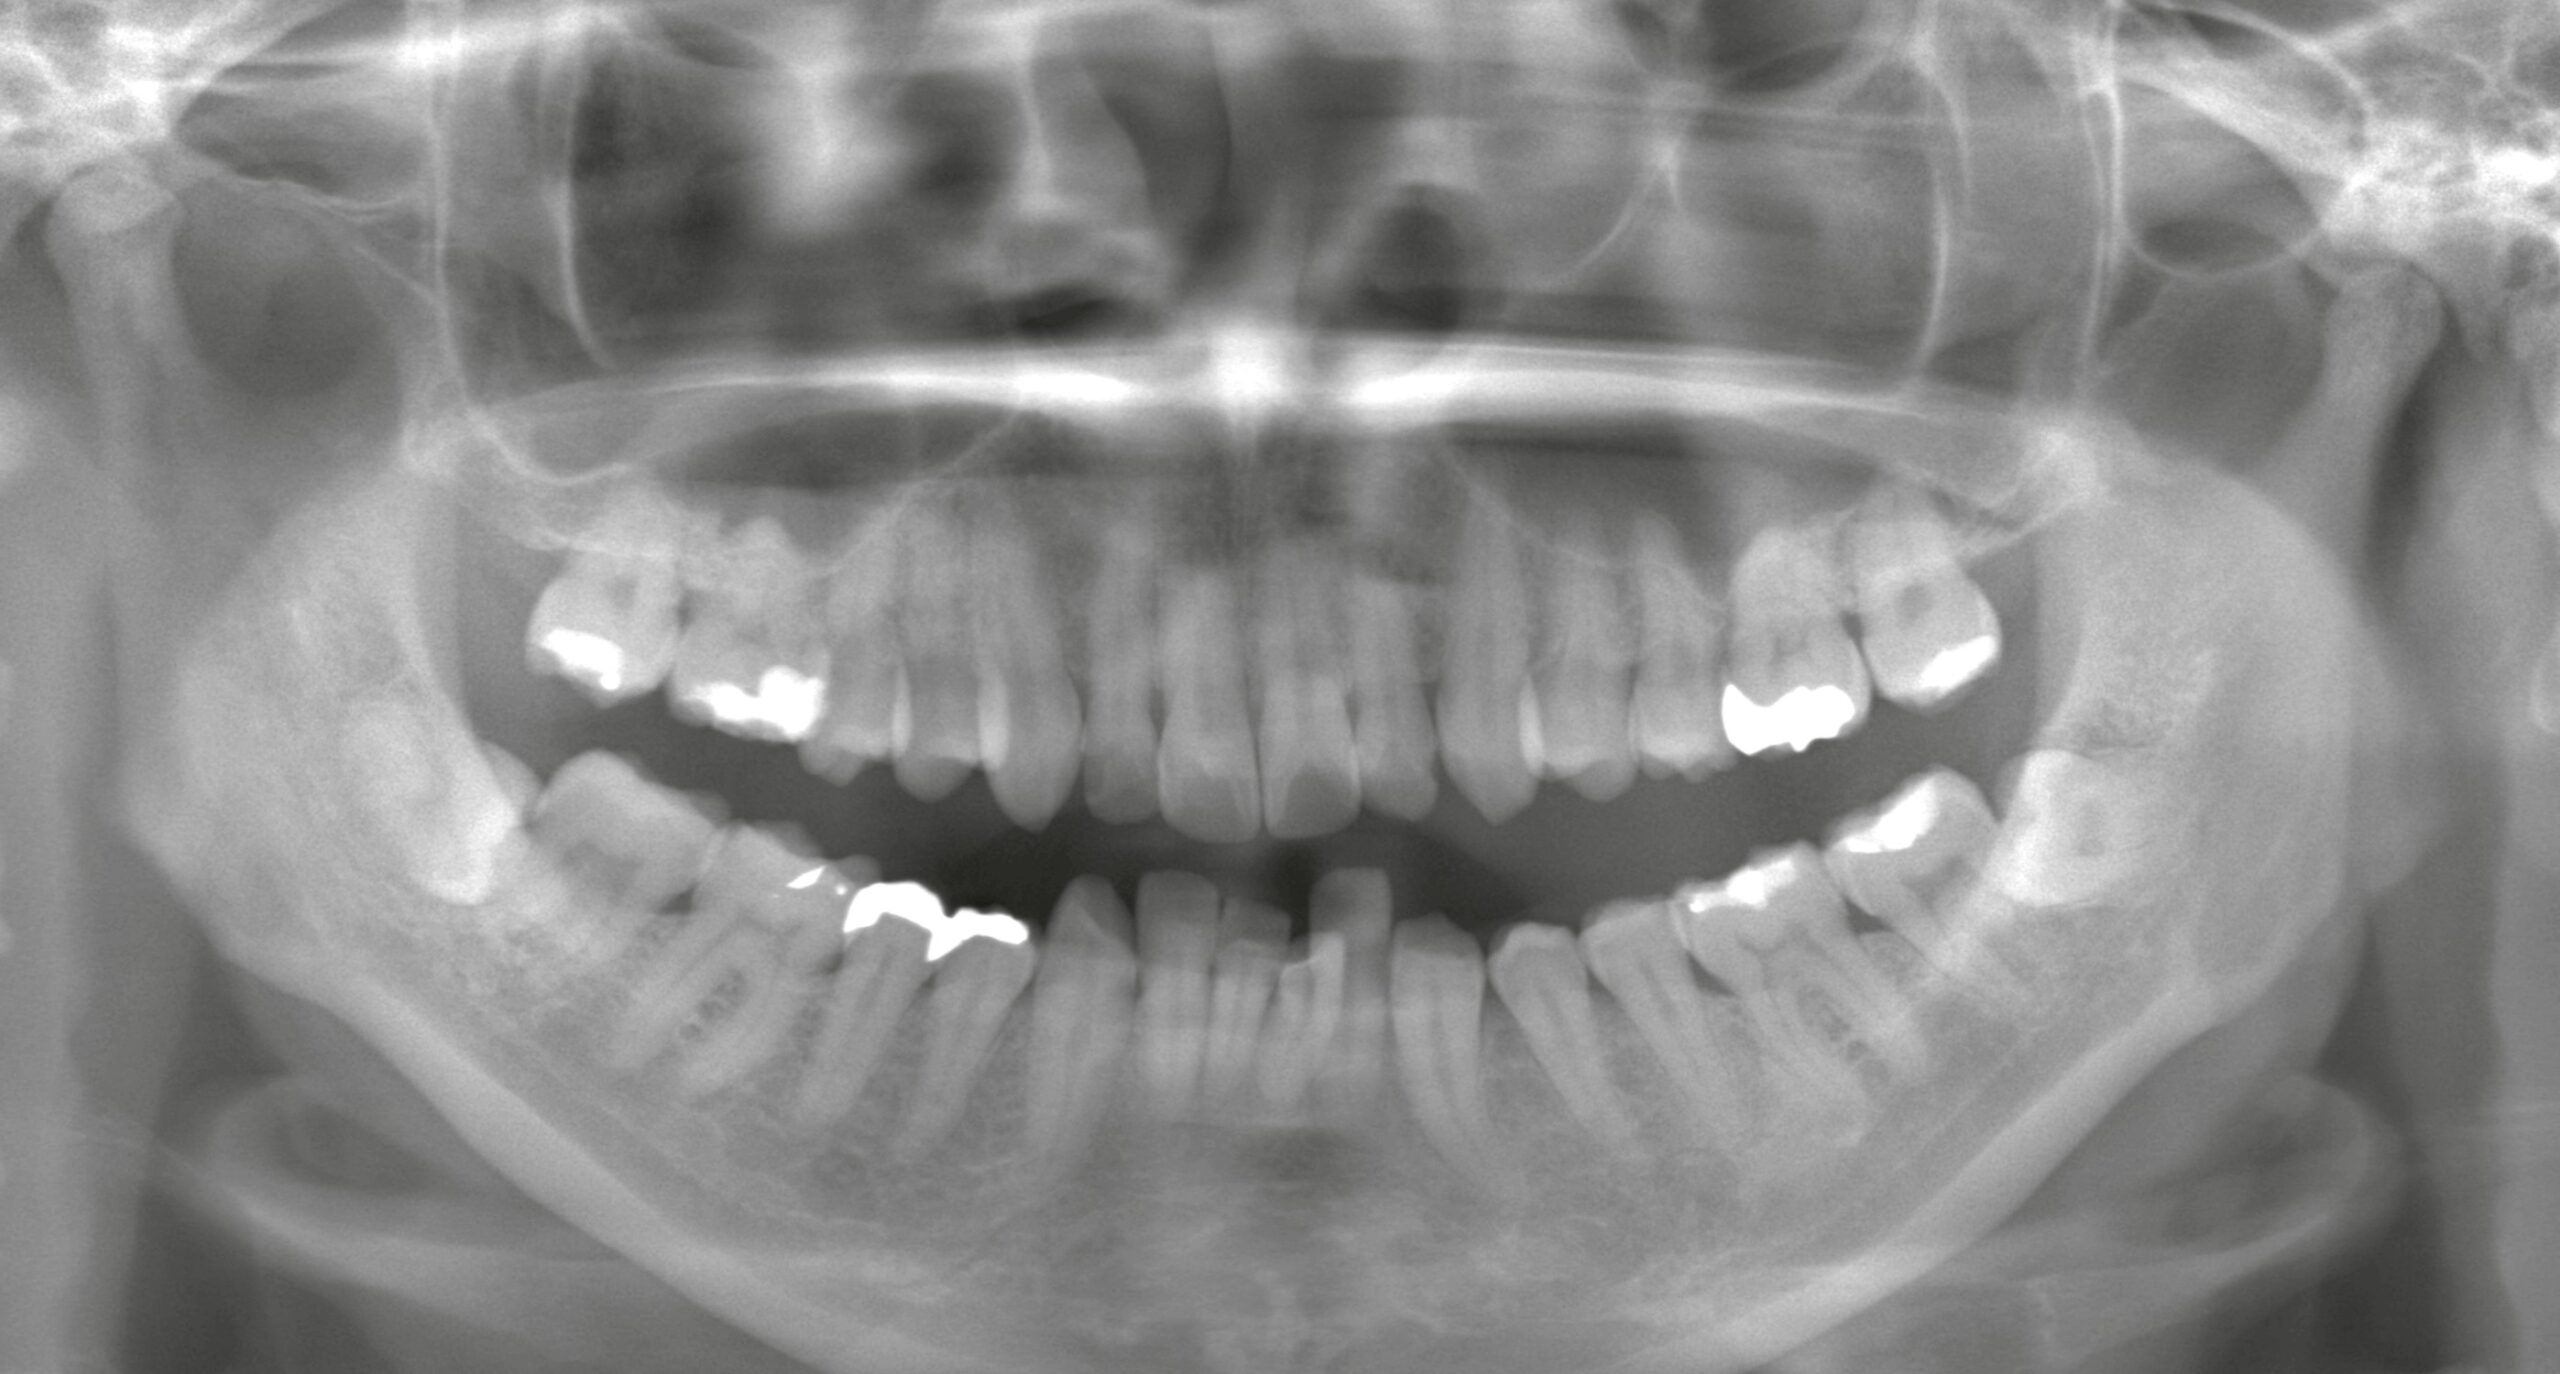

症例紹介

親知らずの抜歯や顎関節症の治療では、患者様の不安や症状にしっかり寄り添いながら、安心・安全な治療を提供しています。

「難しいと言われた親知らず」「顎の不調が治らない」などのお悩みは、ぜひ一度、当院へご相談ください。

特徴4高精度診断を可能にする「歯科用CT」 -